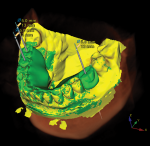

Software that allows for the union of CBCT image files (DICOM) and digital impression files (STL) is essential in the overall digital workflow. However, the mere fusion of this information is not sufficient. The software utilized also must allow for the complete, detailed planning of the final restoration as well as the corresponding implant position, in the same program (eg, the authors use NobelClinician® Software; nobelbiocare.com) (Figure 1). The digital workflow can then be fully realized by precisely planning the 3D position of the final restoration and the technical aspects of the final restorative design to facilitate ideal and proper implant placement. The planned implant placement must allow for the correct biological outcome as well as provide the necessary environment needed for the restorative design to become a reality. The implant placement, which is calculated using a 4-dimensional perspective,1 can then be transferred from the digital workflow to the oral cavity via guided surgery. This is a key aspect of the digital workflow. The fulfillment of digital implant planning through the use of a 3D-printed surgical guide allows for the implant to be placed in the most predictable fashion with the highest level of precision and accuracy, thereby ensuring the surgical outcome mirrors the planned outcome.2